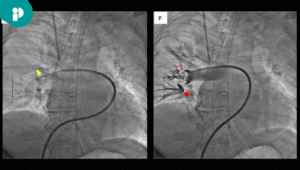

- REBOA (Resuscitative Endovascular Balloon Occlusion of the Aorta)